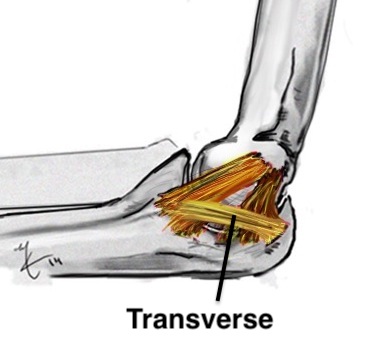

Anatomy of Ulna Collateral Ligament (UCL)

Provides valgus stability

Three components

| Anterior band | Posterior band | Transverse band |

Does not cross elbow joint Does not contribute to vaglus stability |

Medial olecranon to medial coronoid |